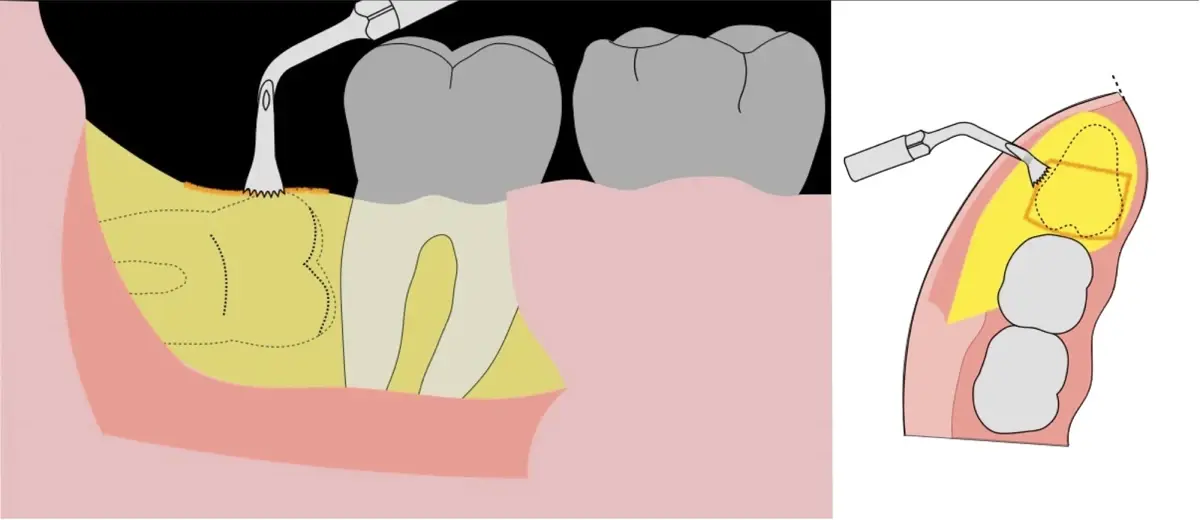

El procedimiento se inicia colocando anestesia troncular para bloqueo del nervio dentario inferior y sus ramas. Luego, se establecerá el diseño de acceso según la disposición de la molar a extraer. Para fines didácticos, se explicará cómo se realizaría la extracción de la molar de la Figura 1: se realiza una incisión horizontal a nivel de la zona retromolar hasta llegar a distal de la segunda molar, continuándose con una incisión intrasurcular hasta mesial de la segunda molar, finalizando con una incisión vertical a espesor total hasta llegar a la línea mucogingival (Figura 2).